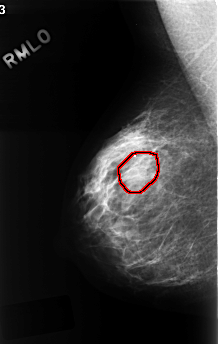

C_0330_1.RIGHT_MLO

RIGHT_MLO LINES 4464 PIXELS_PER_LINE 2824 BITS_PER_PIXEL 12 RESOLUTION 50 OVERLAY

FILE: C_0330_1.RIGHT_MLO.OVERLAY

TOTAL_ABNORMALITIES 1

ABNORMALITY 1

LESION_TYPE MASS SHAPE OVAL MARGINS OBSCURED

ASSESSMENT 3

SUBTLETY 1

PATHOLOGY BENIGN

TOTAL_OUTLINES 1

BOUNDARY